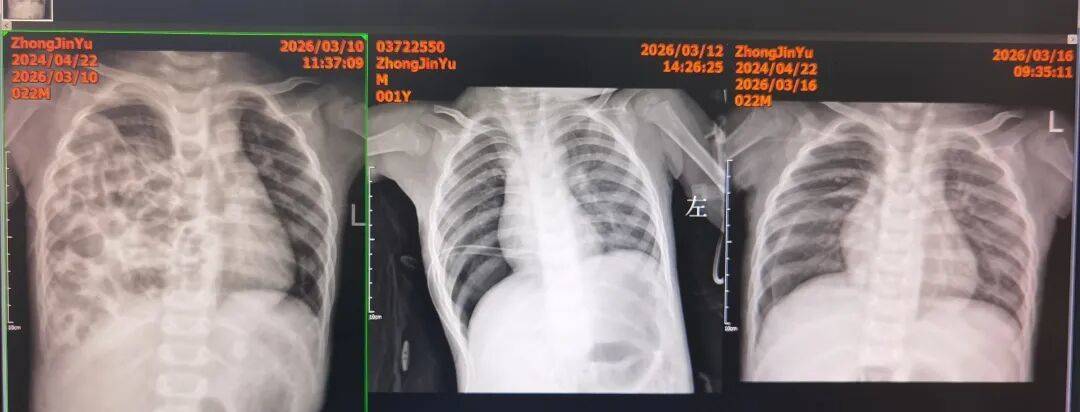

(从左至右)术前:右侧胸腔被肠管完全占据,纵隔移位,心脏偏左;

术后:膈肌恢复完整,右肺顺利复张,胸腔引流管位置良好;

拔管后复查:双肺复张理想,患儿呼吸功能快速改善。

术后第四天,复查胸部DR:右侧膈肌完整恢复,右肺复张良好。拔除胸腔引流管后,孩子呼吸平稳,精神状态明显好转。不久前,小雨的检查报告显示其双肺复张良好,膈肌完整,小雨终于闯过了所有难关,顺利出院。